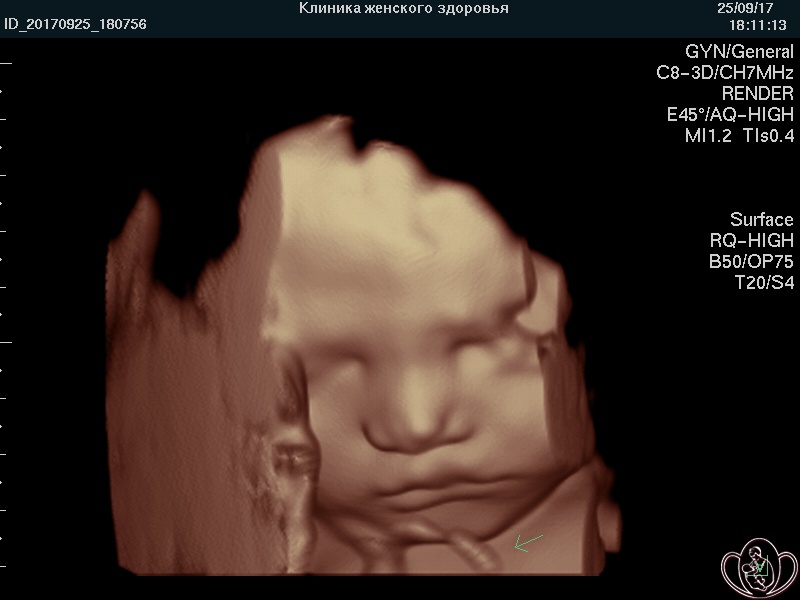

Плод на 38 неделе беременности . Вес ребенка на 38 неделе беременности, как и его рост, продолжает увеличиваться день ото дня . Масса тела достигает 3 кг, а рост - 50 см .

Как ведет себя плод на 38 неделе беременности . У малыша на сроке 38 недели хорошо развились все органы, вся система подготовлена и функционирует для того, чтобы появиться на свет ( 38 неделя беременности показана на фото . . .

Плод на 38 неделе беременности: шевеления, вес и размеры Хоть роды могут произойти в любой из дней этой недели, пока они не наступили - беременность продолжается .